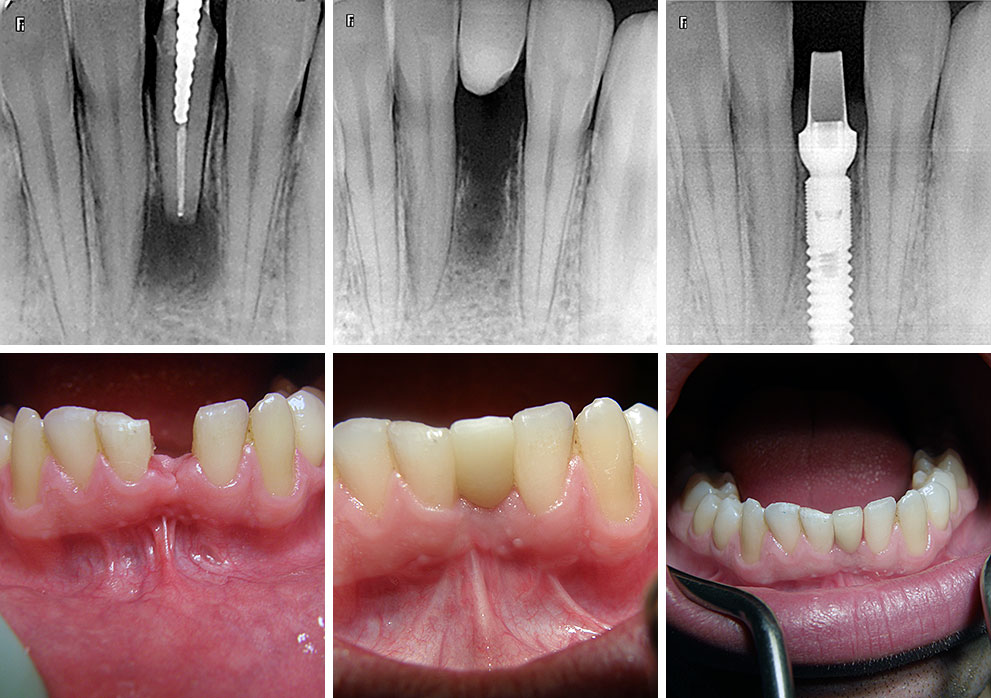

Implantologija